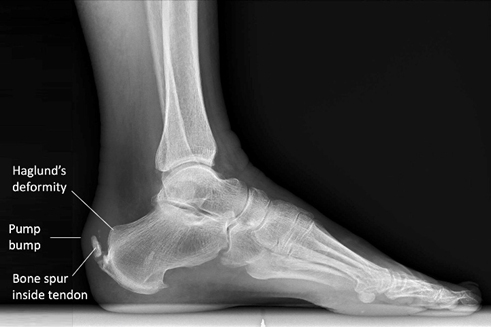

At times heel spurs develop on the back of the heel and impinge on the Achilles tendon or inflame the calcaneal Bursa leading to Achilles tendinitis or calcaneal Bursitis. Achilles Tendinitis is a condition where the Achilles tendon, which connects calf muscle to the heel bone, becomes inflamed and irritated.

Haglund’s deformity. This is a condition in which there is enlargement of the bone on the back of the heel. This can rub on the Achilles tendon and cause inflammation and pain.